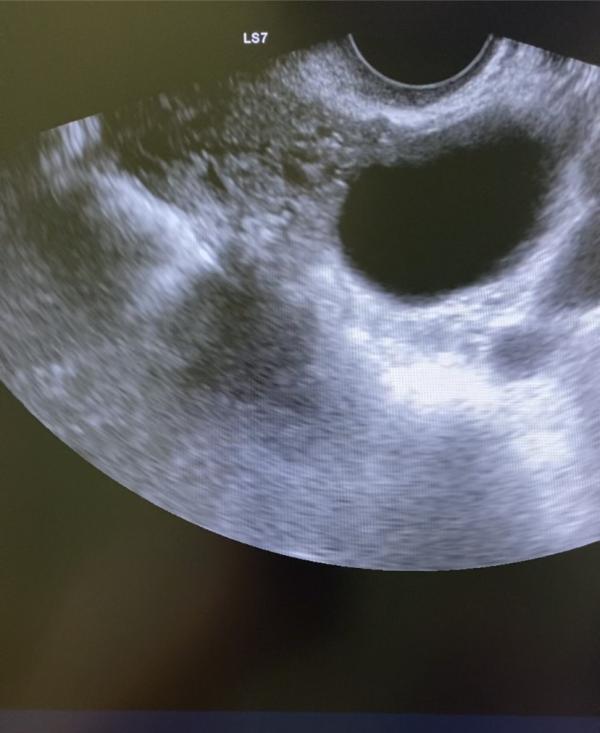

Совместно с лечащим врачом подберите подходящий метод контрацепции . Это лучше чем аборт !

Ужас... Страшно читать даже...